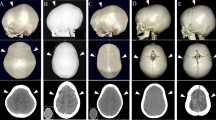

The child underwent lateral tarsorrhaphies for proptosis eye management. The posterior cranial decompression by wide craniectomy was performed along with foramen magnum decompression at the age of 2 months (Fig. 1). This involved a meticulous dissection of the bony spicules projection into the dura, resulting in a wide bony excision from just posterior to the fused coronal ring of sutures back to and including the posterior rim of the foramen magnum. The intraoperative blood salvage was used to reduce the transfusion to 35 ml. One month after surgery, the shape of the head appeared rounder and more expanded posteriorly (Fig. 2A, E). Despite this decompression, the hydrocephalus has been progressive and managed by undergoing a programmable ventriculoperitoneal (VP) shunt 2 months after the primary cranial surgery.

A, E One month after posterior cranial decompression. The head shape looks rounder and fully expanded posteriorly. B, F Eleven months after posterior decompression. It shows a metopic ridge and trigonal-turricephalic head shape. C, D, G, H At 14 months after primary surgery (16 months of age), the fronto-orbital advancement and cranial remodelling were performed to correct the head shape and expand the intracranial volume

Follow-up CT at postoperative 4 months after primary decompression (at 6 months of age) revealed remarkable cranial expansion in the parieto-occipital area and improved CSF space between the cerebellar and the brain stem. However, the fused metopic suture was observed with the upward medially displacement of the supraorbital area (Fig. 1F). The secondary metopic craniosynostosis with a prominent metopic ridge and trigonal-turricephalic head shape was revealed at the age of 13 months postoperatively (around 11 months after posterior decompression) (Fig. 2B, C, F, and G). The boy’s development is progressively improving and appropriate age.

Fronto-orbital advancement with remodelling was performed at the age of 16 months. The supraorbital bar was advanced 15 mm bilaterally, and the triangulated forehead was reshaped. The prominent turricephalic shape was also decompressed (Fig. 2D, H). Clinical follow-up is ongoing.